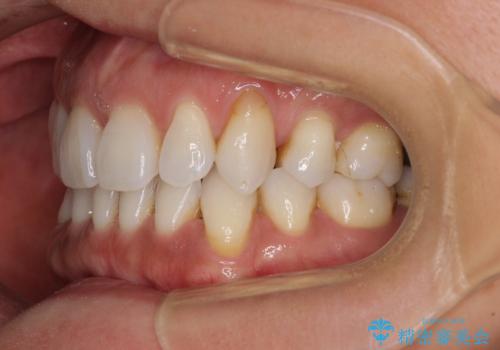

抜歯矯正の後戻りをインビザライン・ライトで解消

- 下顎前歯を中心に、以前行った矯正治療の後戻りが気になるとのことで来院された患者様です。

後戻りは軽度であったため、インビザライン・ライトにて治療を行うこととしました。

矯正治療後は、再度後戻りすることを極力回避するために、下顎前歯の舌側を細いワイヤーを用いて保定することとしました。